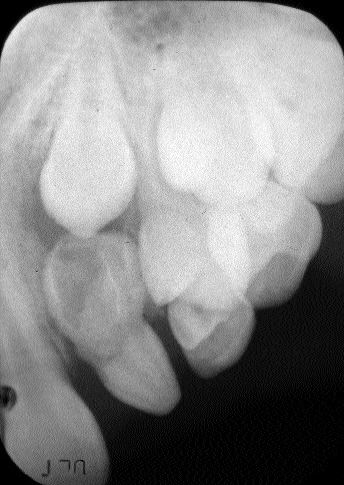

1000194597-1000272441 alternate text for this image

In general most facial infections are of odontogenic origin and they do not normally occur without a predisposing condition.1 These infections can be caused by dental caries or deep restorations that approximate the pulp, infected pulps leading to a periapical abscess, periodontal abcess and pericoronitis. Failure to institute early treatment may result in the development … Read more